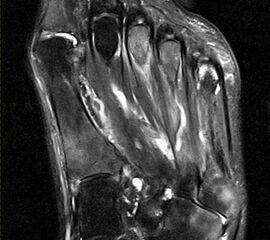

Gicht

Typische Gichtmanifestation an der Großzehe mit Tophusstachel (Pfeil) und großem Tophus, in welchem Uratablagerungen identifiziert werden können (Pfeilspitze). T1-gewichtete Sequenz vor (a) und nach (b) Kontrastmittelgabe, letztere mit Fettsuppression.

Abbildung 15

Dies erst recht, wenn diese Arthritis am Großzehen­grundgelenk auftritt (Abb. 15). In diesen Fällen sollte man den Verdacht auch dann aufrechterhalten, wenn die MRT nur eine unspezifische Entzündung zeigt und die Harnsäurewerte, die starken Schwankungen unterliegen können, nicht erhöht sind.

Spezifische MR Befunde finden sich erst bei der chronischen Gicht, wenn sich in T2 sehr signalarme Kristallablagerungen und Gicht-Tophi bilden. Letztere führen dann häufig zu den aus der Röntgendiagnostik bekannten gelenkfernen Erosionen.

Abbildung 15: Typische Gichtmanifestation an der Großzehe mit Tophusstachel (Pfeil) und großem Tophus, in welchem Uratablagerungen identifiziert werden können (Pfeilspitze). T1-gewichtete Sequenz vor (a) und nach (b) Kontrastmittelgabe, letztere mit Fettsuppression.